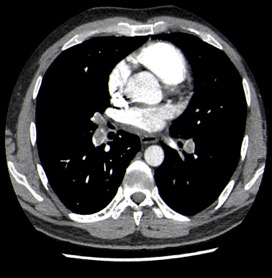

Nuestro paciente tiene síntomas respiratorios y un valor elevado de Dímero D. El Angio-TC nos permite hacer una valoración más detallada del estado de la anatomía vascular pulmonar así como del del corazón: También nos va a proporcionar una visión más en detalle del parénquima pulmonar.